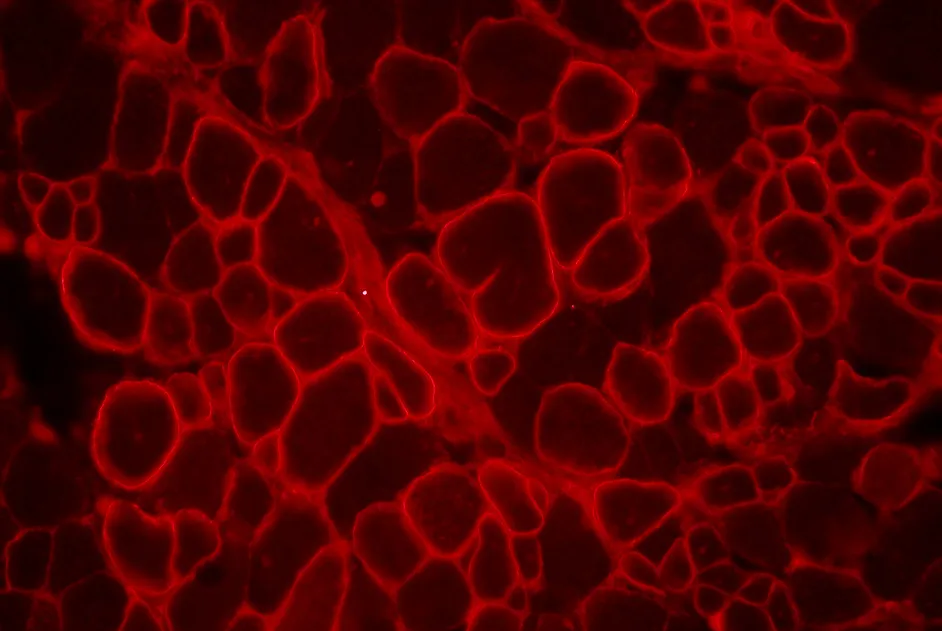

Une équipe française, soutenue par l’AFM, a développé un nouveau modèle de myopathie de Duchenne, avec fibrose : la souris fib-mdx.